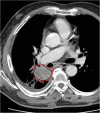

Radiomics is an emerging translational field of research aiming to extract mineable high-dimensional data from clinical images. The radiomic process can be divided into distinct steps with definable inputs and outputs, such as image acquisition and reconstruction, image segmentation, features extraction and qualification, analysis, and model building. Each step needs careful evaluation for the construction of robust and reliable models to be transferred into clinical practice for the purposes of prognosis, non-invasive disease tracking, and evaluation of disease response to treatment. After the definition of texture parameters (shape features; first-, second-, and higher-order features), we briefly discuss the origin of the term radiomics and the methods for selecting the parameters useful for a radiomic approach, including cluster analysis, principal component analysis, random forest, neural network, linear/logistic regression, and other. Reproducibility and clinical value of parameters should be firstly tested with internal cross-validation and then validated on independent external cohorts. This article summarises the major issues regarding this multi-step process, focussing in particular on challenges of the extraction of radiomic features from data sets provided by computed tomography, positron emission tomography, and magnetic resonance imaging.